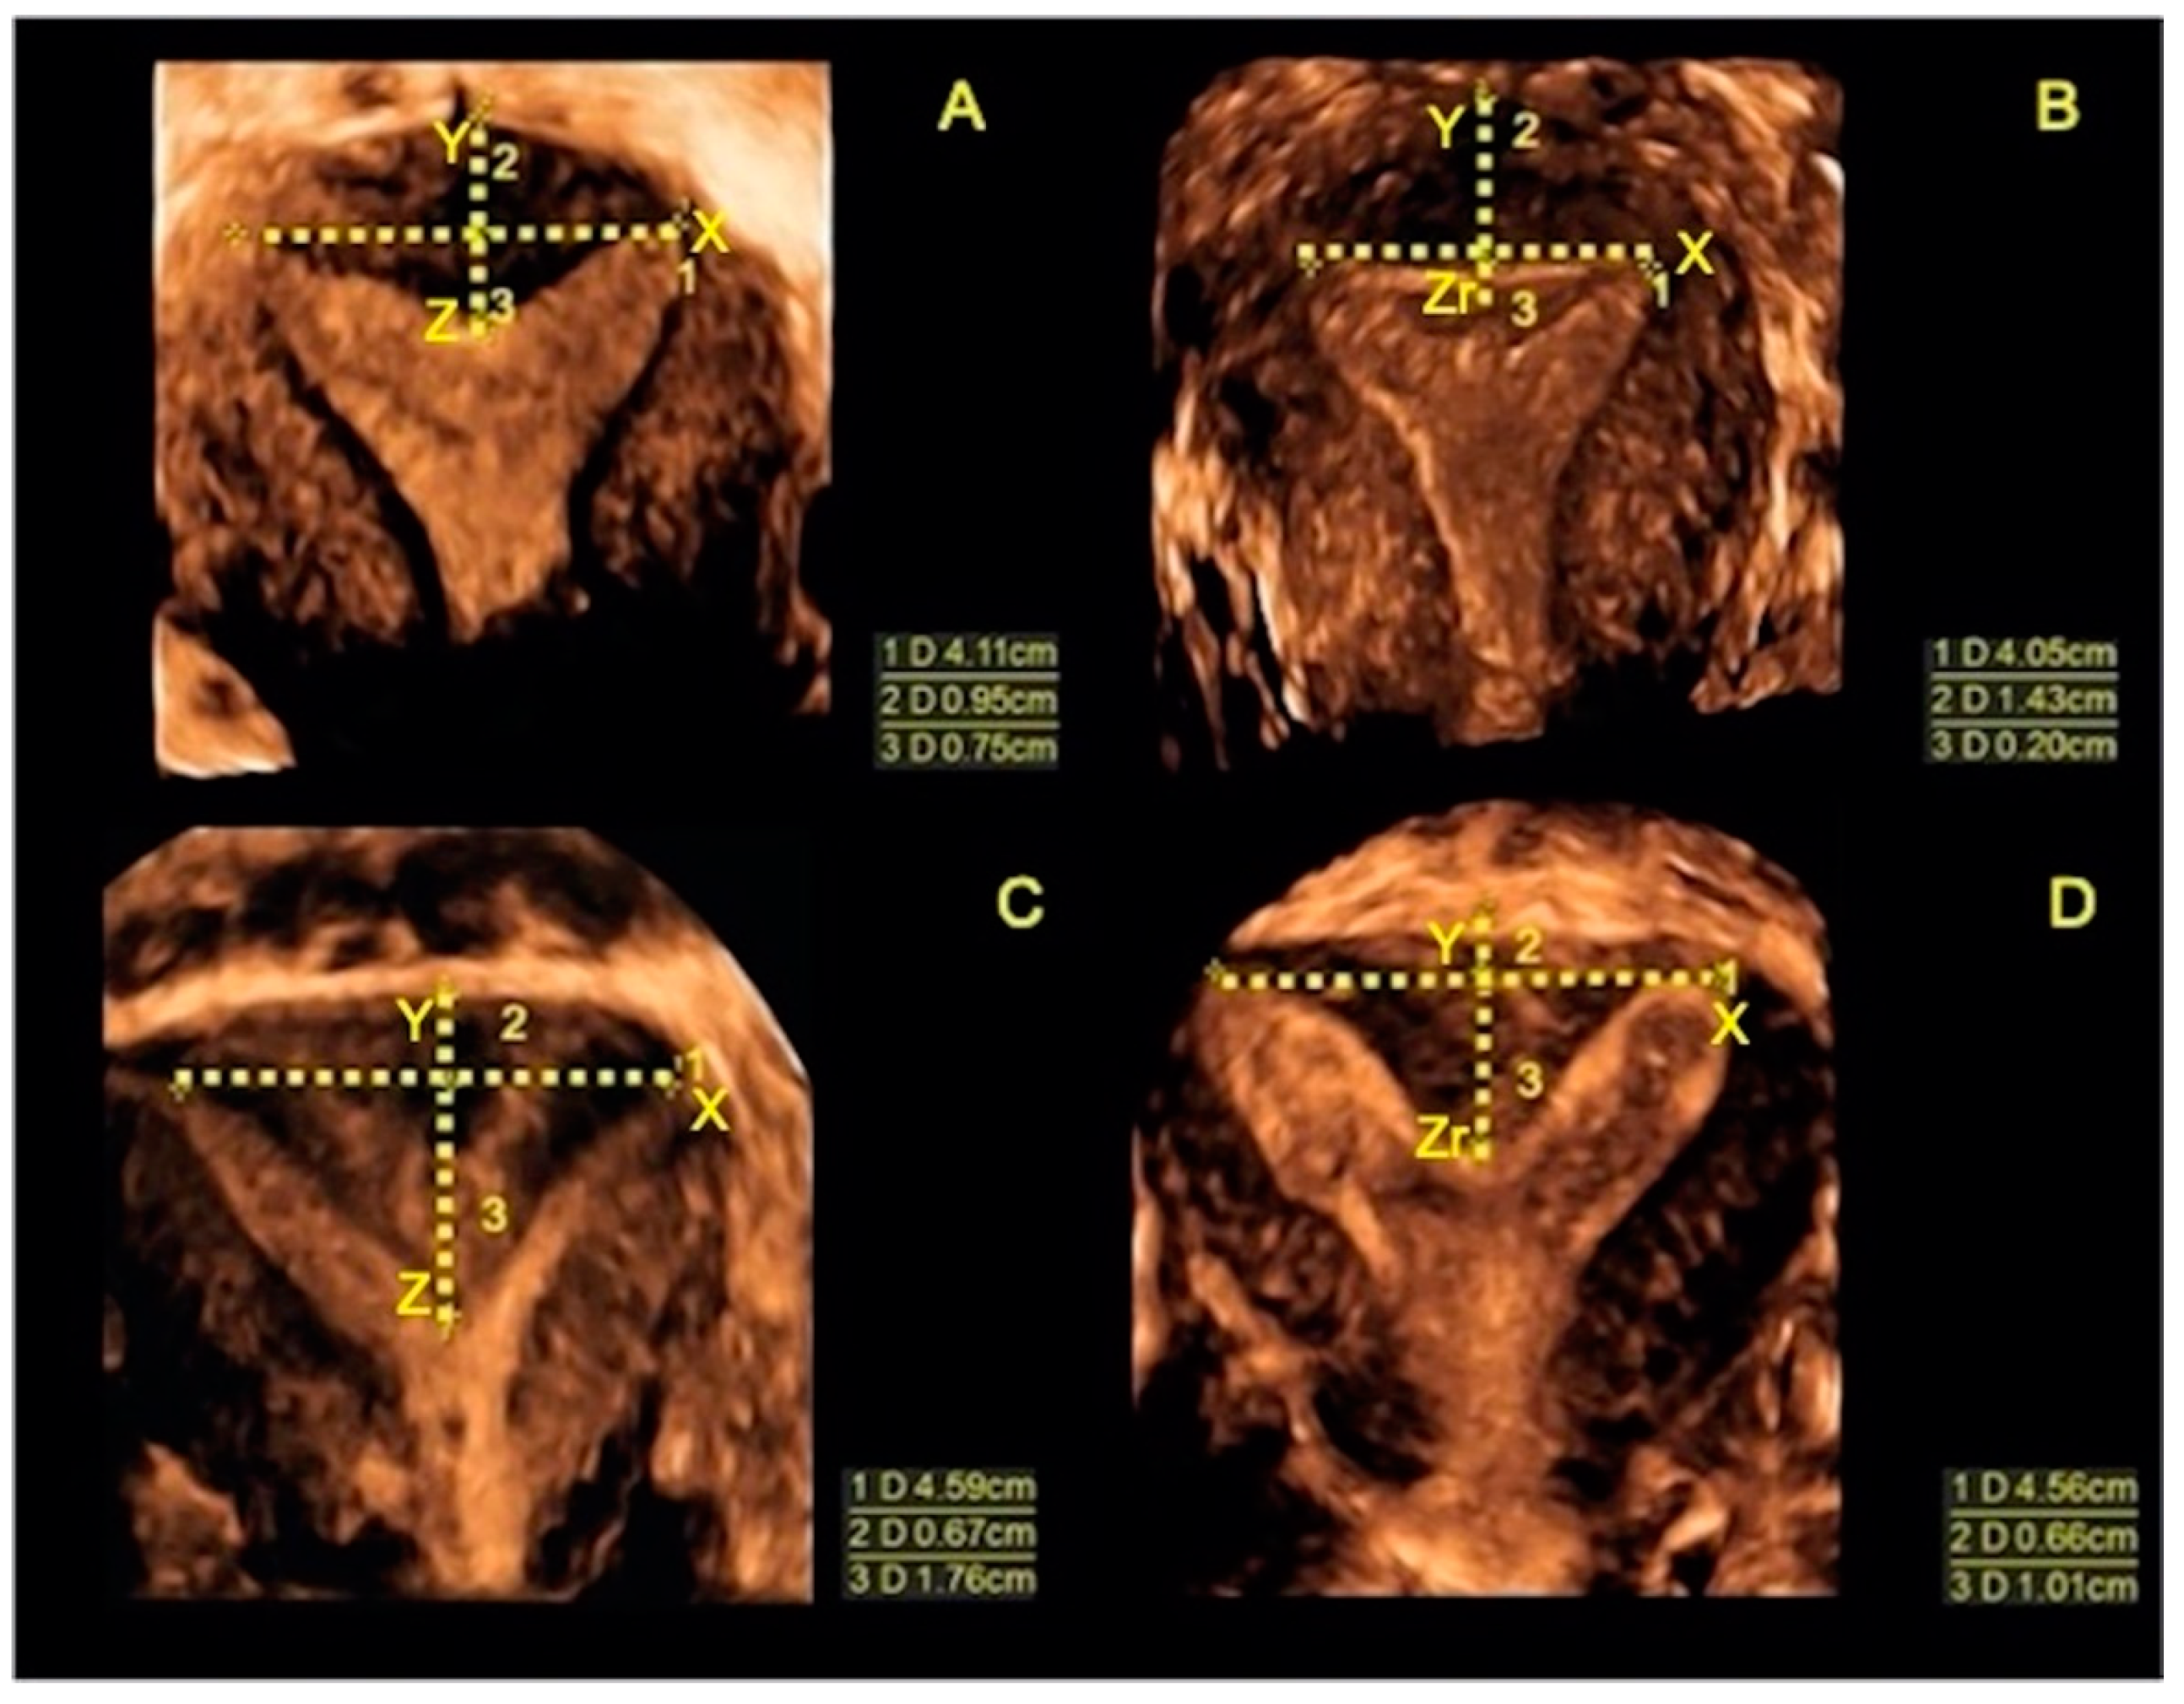

| Length of the septum, Z (mm ± SD) | 24.9 ± 5.13 |

| Thickness of uterine myometrial fundus, X (mm ± SD) | 5.9 ± 1.94 |